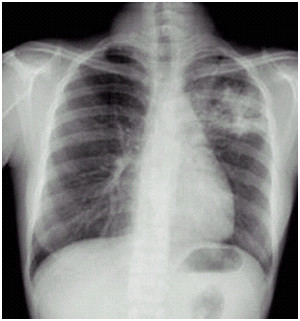

03卷-3.男性,34歲,咳嗽、無痰半月,伴低熱。診斷(本題滿分2.00分)

A.左上支氣管擴張

B.左上肺炎

C.左上浸潤型肺結(jié)核

D.左側(cè)胸腔積液

本題答案:C

題目解析:

【該題針對“ X線-浸潤型肺結(jié)核 ”知識點進行考核】